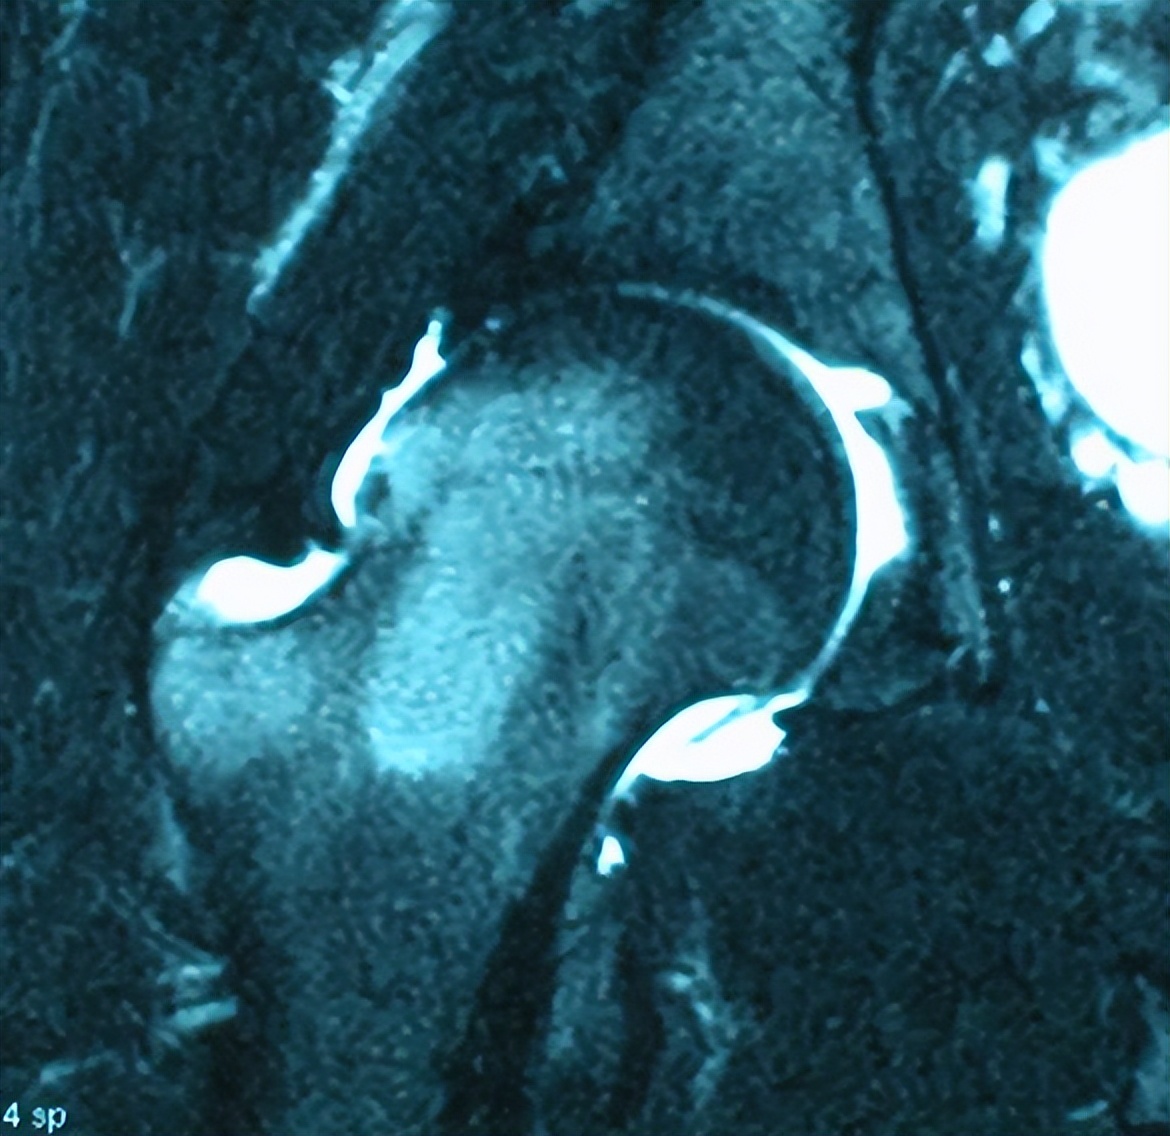

髋关节MRI检查报告征象描述:右髋关节对位可,髋关节面下骨髓水肿。股骨头颈交接区骨质略隆起,皮质下骨内可见小片状T2高信号,关节腔积液。

X线检查报告征象描述:双髋关节对位可,关节间隙不窄,髋臼缘骨质增生硬化,双侧股骨头骨质及形态未见明显异常。初步判断为可能是髋关节撞击综合征、盂唇撕裂疾病。